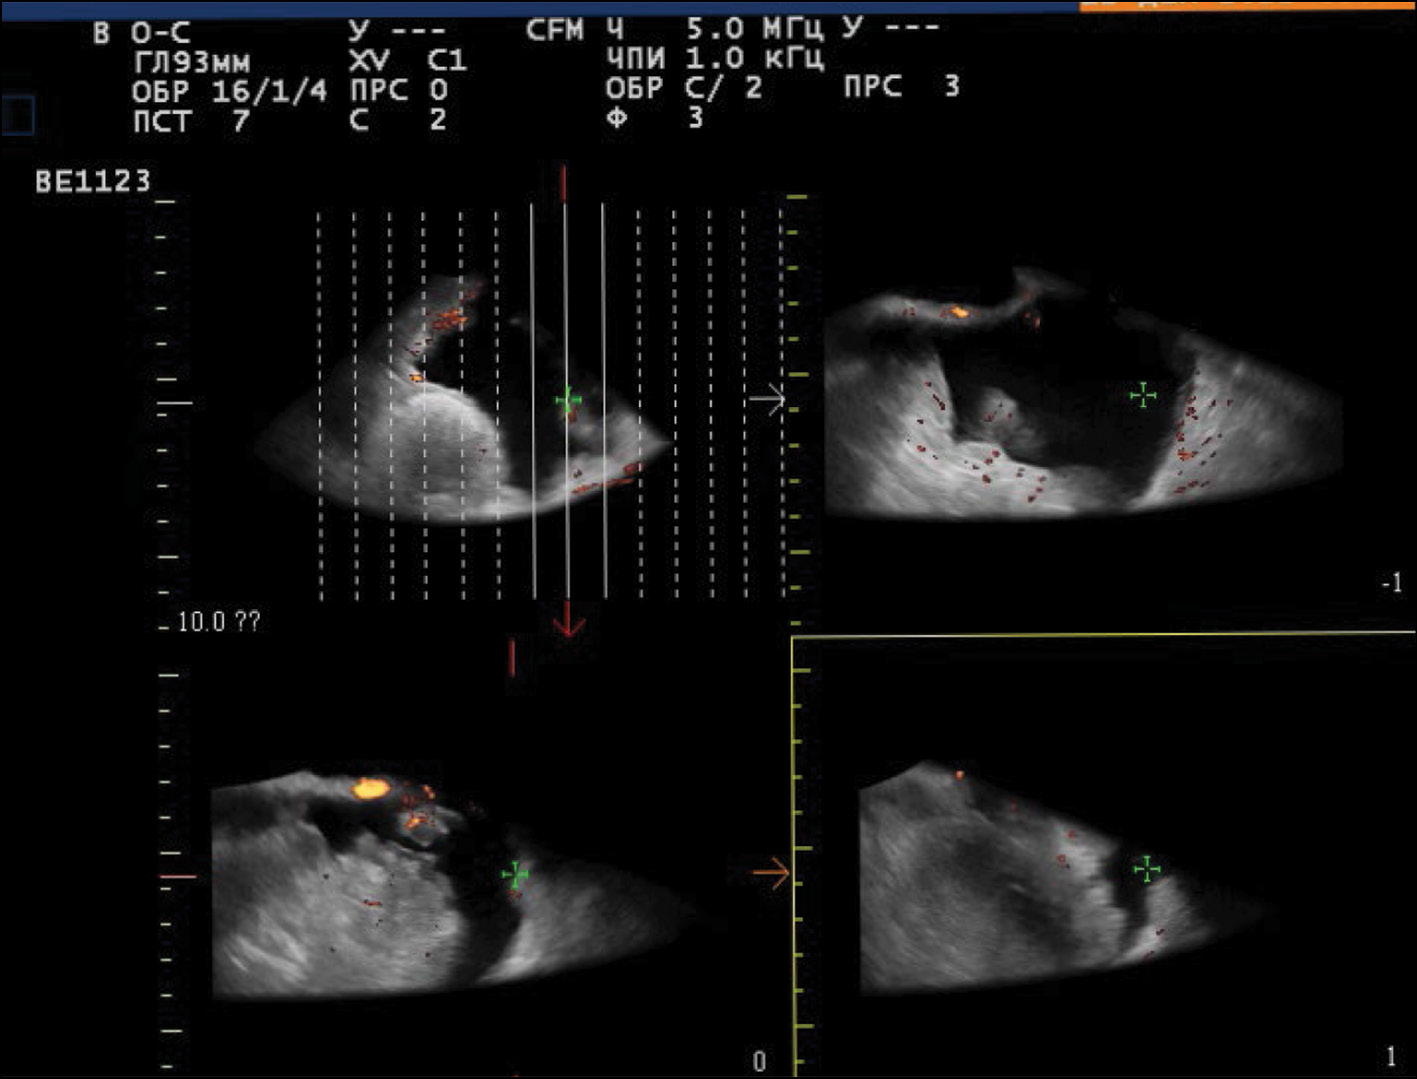

US demonstrated that the recurrent lesion of malignant struma ovarii along the pelvic peritoneum, identified in the presence of ascites, had an iso-hypoechoic structure with fuzzy contours and small size (4–12 mm). The peritoneum of the small pelvis outside the lesion was <4 mm thick; however, 3D angiography and US-CT revealed that even small blastomatous lesions were well vascularized. Blood flow was also present in the 4–5 mm thick structure of the pelvic peritoneum (Figs. 5–7).

Fig. 5. Dopplerography in the energy mode. The arrows show recurrent lesions of the malignant struma ovarii.

Fig. 6. US-CT of the recurrent lesions of the malignant struma ovarii.

To identify specific US signs of malignant struma ovarii, recurrent tumor lesions along the peritoneum of the malignant struma in one patient were compared with recurrent lesions of serous ovarian adenocarcinoma in 12 patients. When comparing the tumor lesions in the retrouterine space, a more pronounced neoangiogenesis was noted in the tumor lesion of the malignant struma ovarii, where the peak systolic velocity (PS) was recorded in small lesions (4–12 mm) and ranged from 2 to 9 cm/s. The maximum vascular resistivity index (RI max) was 0.53. No blood flow was noted in recurrent lesions along the pelvic peritoneum of the serous adenocarcinoma up to 9 mm, and in lesions up to 15–20 mm, PS varied from 2 to 4 cm/s or was <2 cm/s (Figs. 5 and 8).